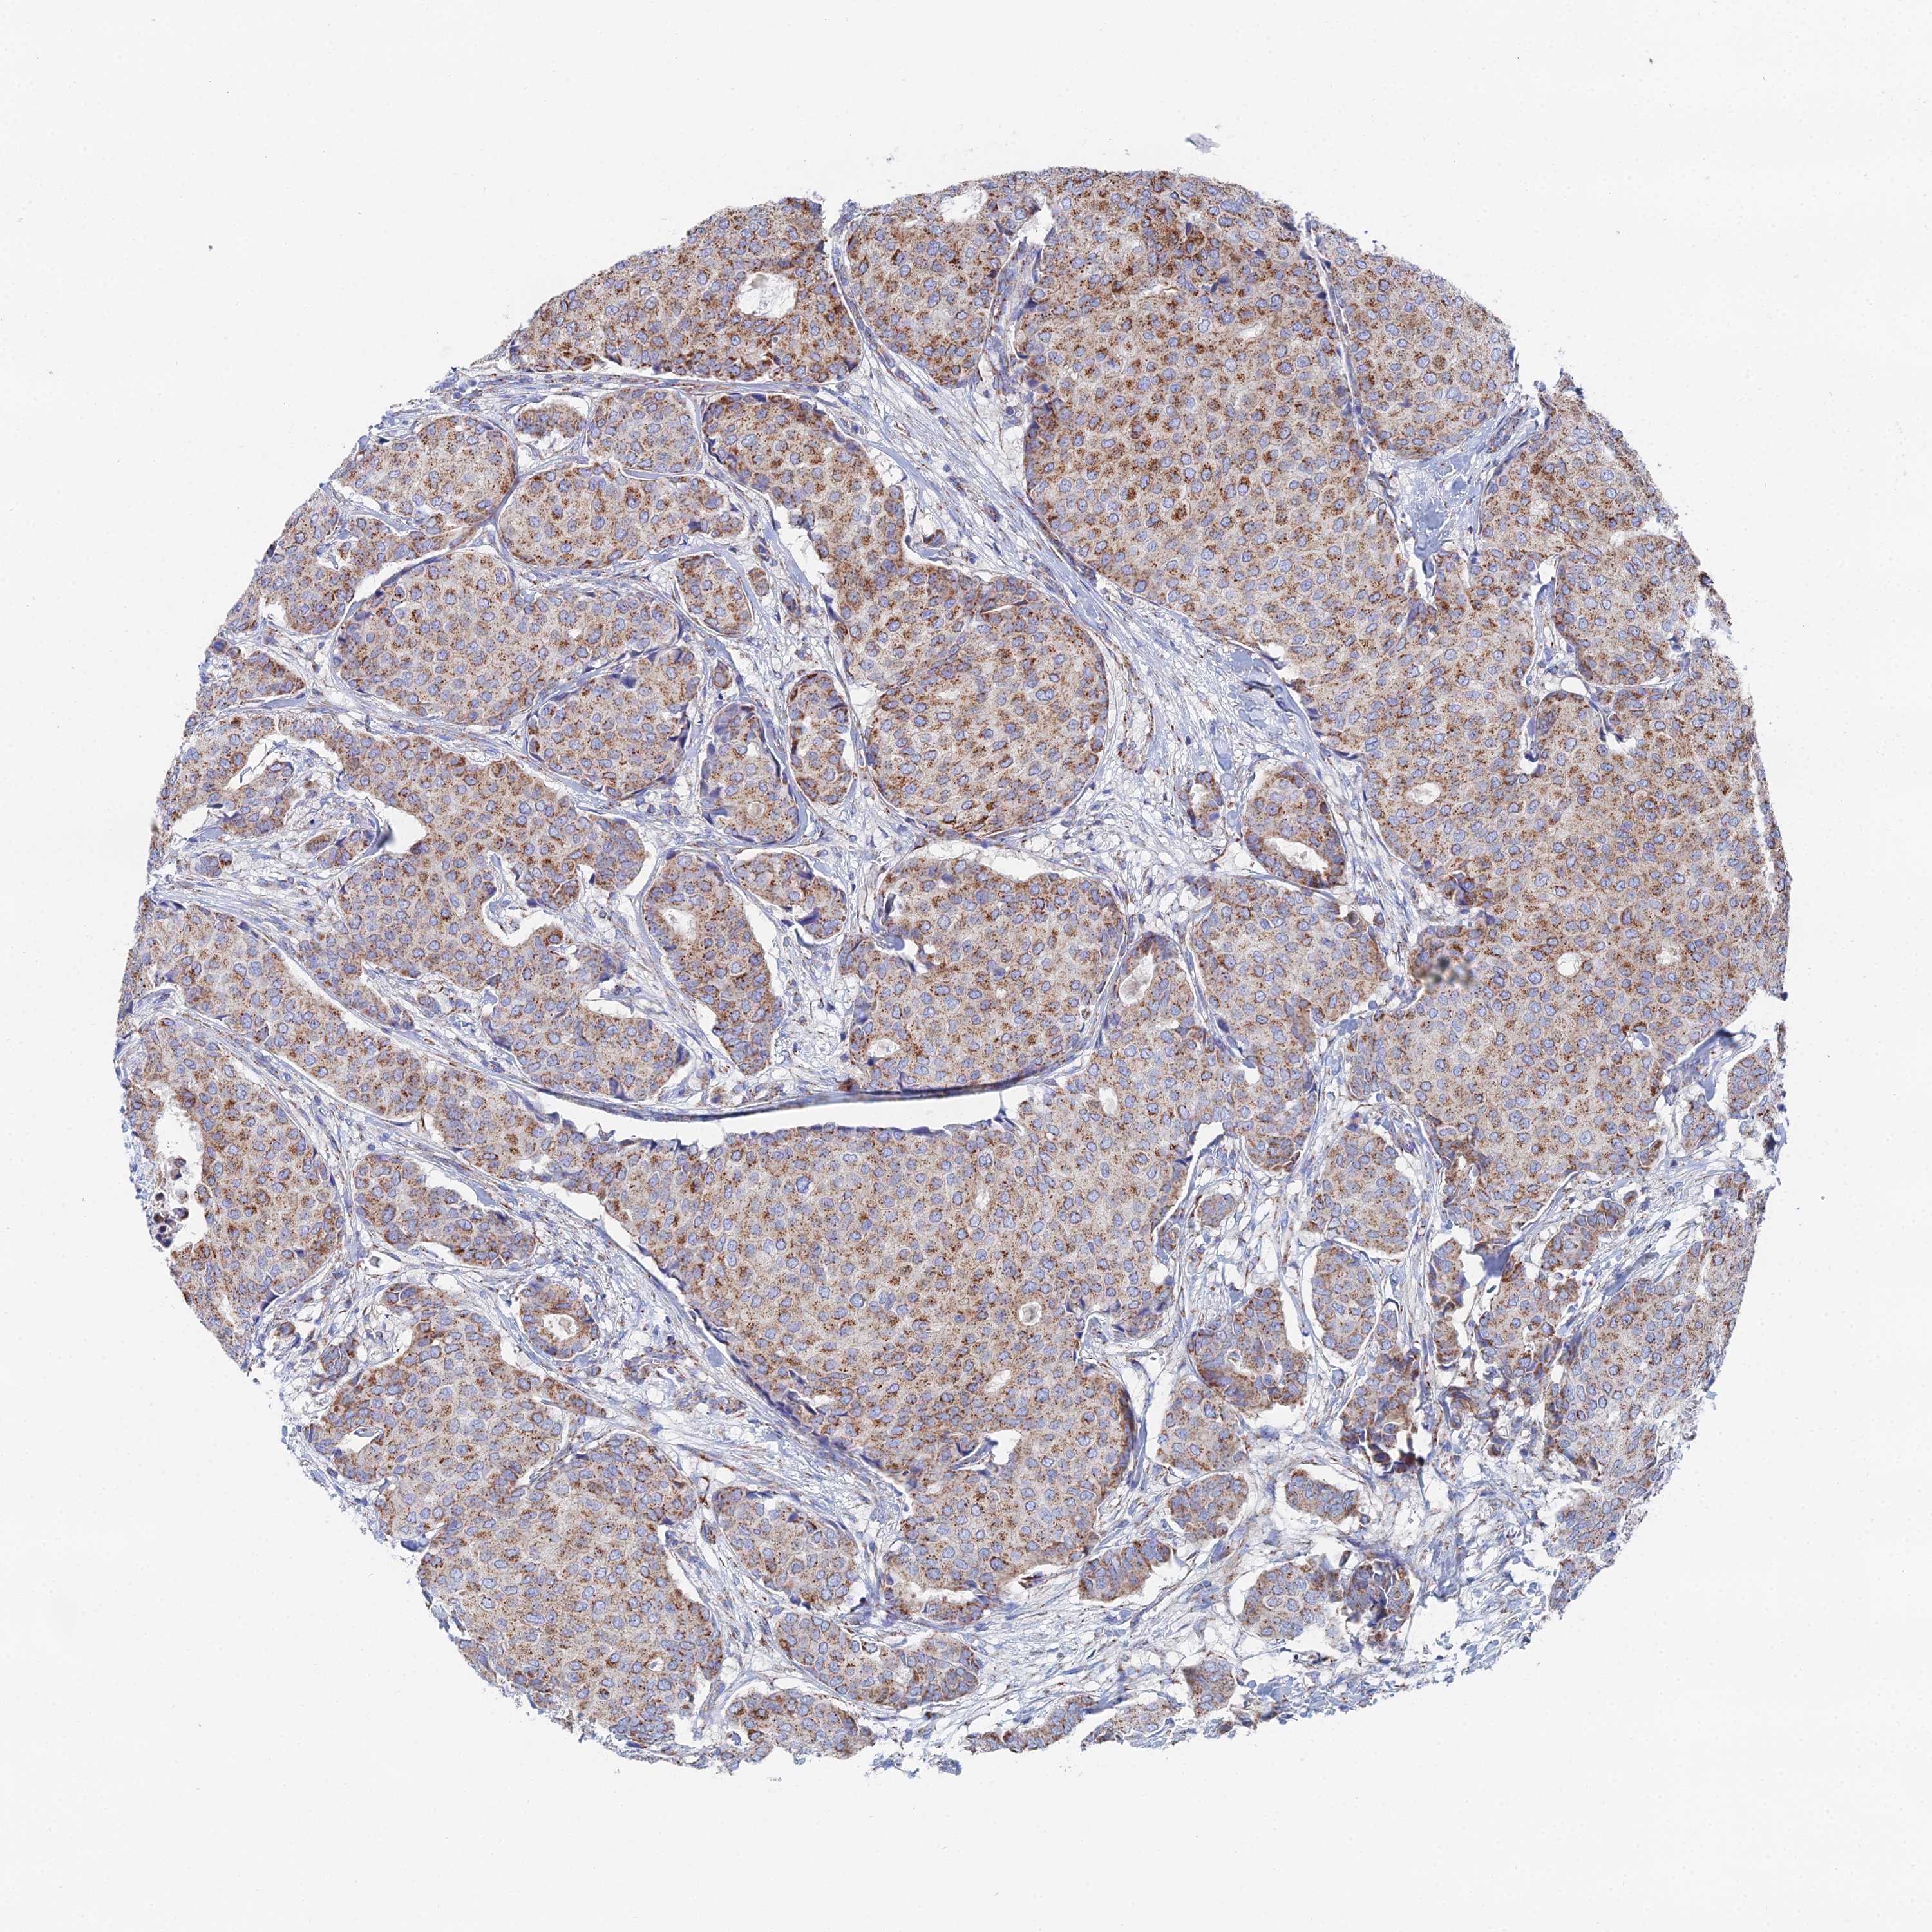

CANCER BREAST CANCER Show tissue menu

BRCA TCGA BRCA VALIDATION PROTEIN EXPRESSION

Breast cancer

Human cancer